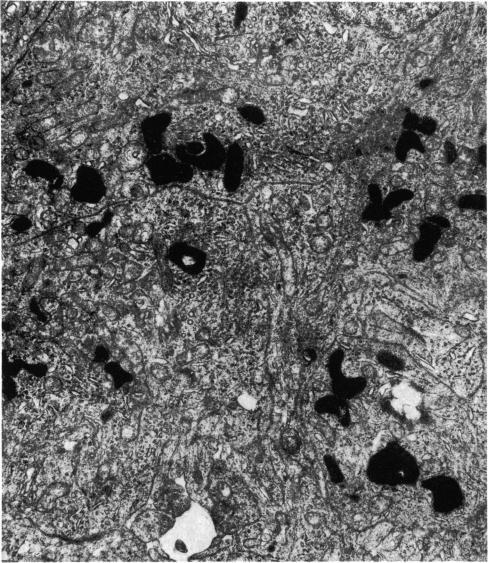

The pineal gland of chicks treated with oestrogens and androgens has been studied histochemically and ultrastructurally from post-hatching until 90 days of age. The results obtained may demonstrate a precocious maturity of the gland caused by its response to the early high level of sex hormones circulating in the blood.

对用雌激素和雄激素处理过的雏鸡的松果体进行了组织化学和超微结构研究,研究从雏鸡孵化后直至90日龄。所获得的结果可能表明,由于松果体对血液中早期高水平性激素的反应,该腺体出现早熟。